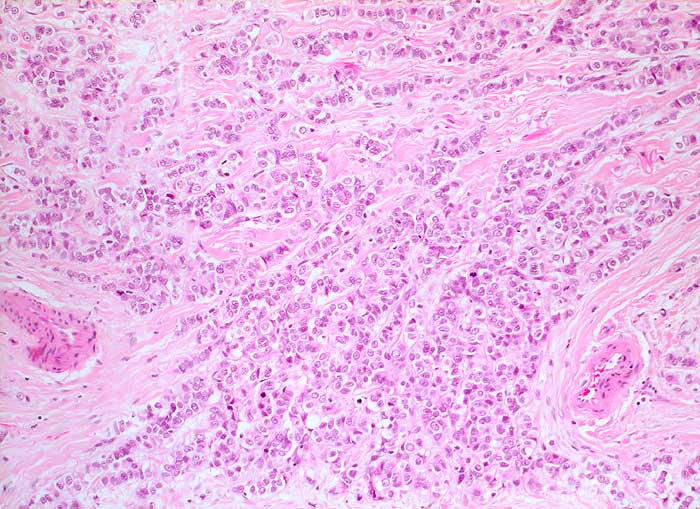

invasiv lobuläres Mammakarzinom

Die monomorphen Tumorzellen sind in Einerreihen angeordnet. Zwischen den Zellreihen desmoplastisches Stroma.